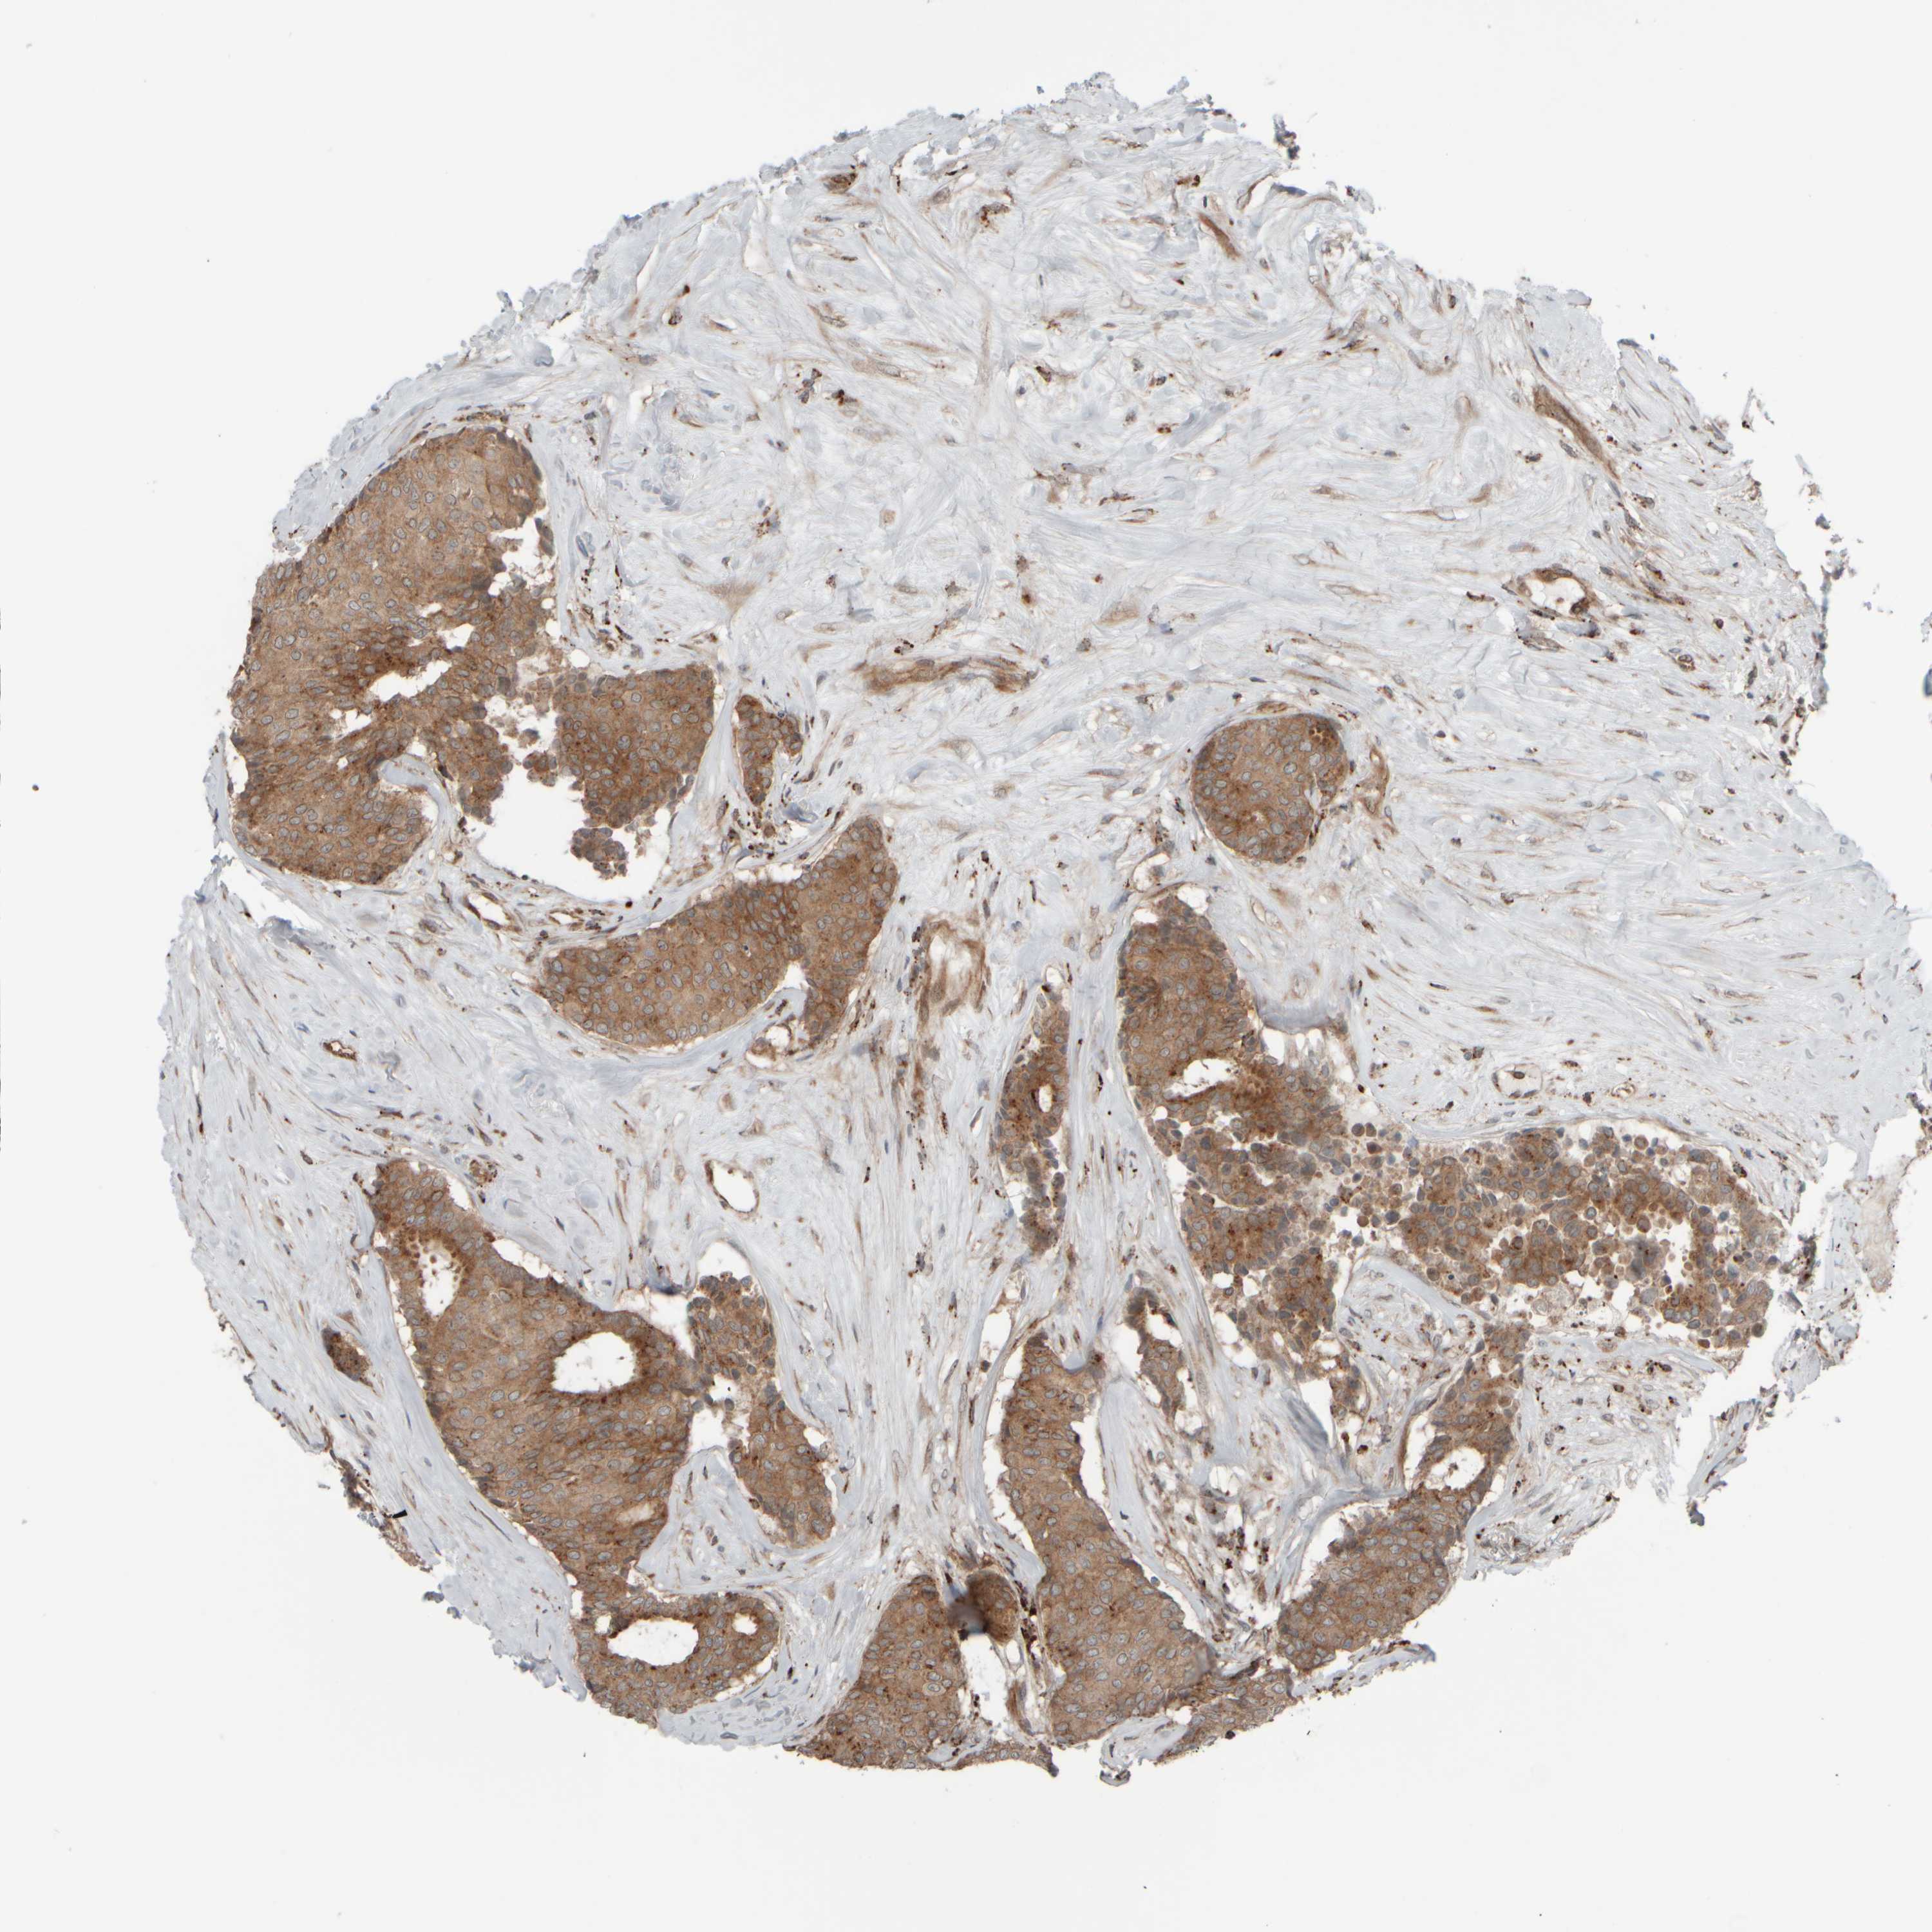

CANCER BREAST CANCER Show tissue menu

BRCA TCGA BRCA VALIDATION PROTEIN EXPRESSION